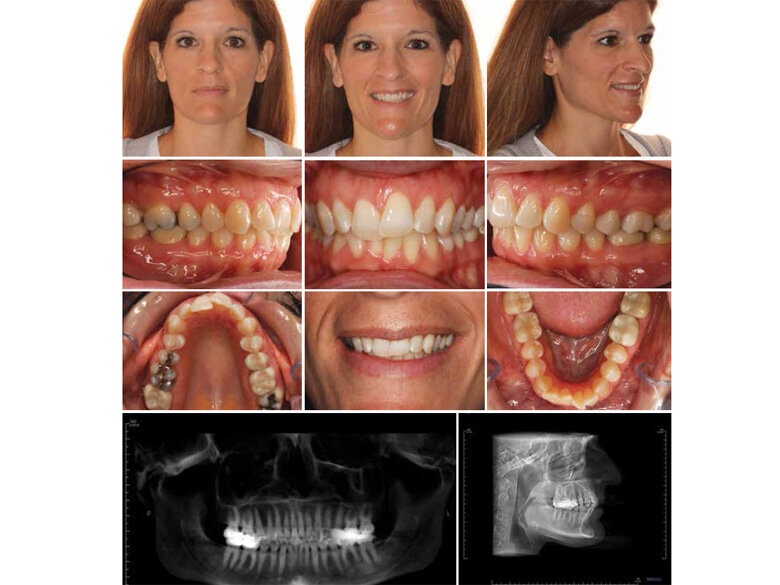

Fig. 5: Final recods. (Photos: Michael J. Mayhew, DDS, MS, MS, & Nicole R. Scheffler, DDS, MS)

The efficiency of Spark Clear Aligners is demonstrated in the following case report. Initial diagnostic records (Fig. 4) were obtained for the patient who offered a chief complaint of “upper front teeth bothering her and getting worse.” Her desire was to have clear aligner treatment and for it to be as fast as possible. The treatment plan included arch width development, uprighting of the teeth and angulation corrections, and ideal alignment with the potential for interproximal reduction. A vibratory intraoral appliance with directions to use 20 minutes per day was utilized with the initial 33 aligners. An additional 16 refinement trays were utilized with treatment completed in eight months (Fig. 5). Appropriate retention appliances were placed with completion of treatment for a very excited and happy patient!